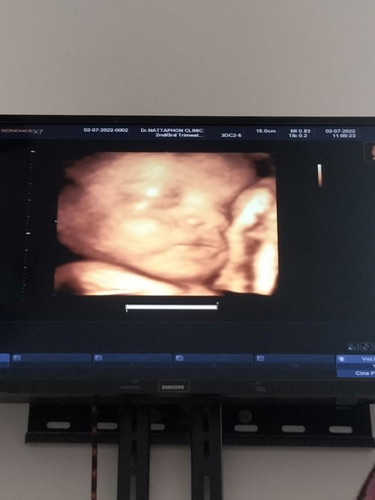

อยากเจอหน้าน้องแล้วค่ะ

32+4วีคน้องหนัก2062กรัม คุณหมอบอกน้ำหนักน้องตามเกณฑ์ดีแต่อิแม่ไม่รอดเบาหวานจ้ากลืนน้ำตาลวันนี้50กรัม ค่าได้160เลย😭😭